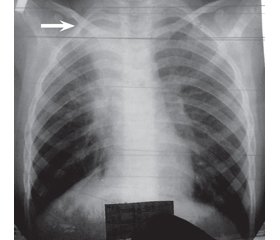

Проведена рентгенографія органів грудної клітки в проекції S1–2, виявлена ділянка інтенсивного затемнення з вираженими контурами. Клінічні і рентгенологічні дані дали підставу для встановлення діагнозу позалікарняної правобічної сегментарної (S1–2) пневмонії (рис. 2).

У динаміці спостереження стан дитини погіршився: наростала дихальна недостатність, оксигенозалежність, дихання ставало ослабленим над всією поверхнею правої легені. Комп’ютерна томографія легень в спіральному режимі кроком 3 мм при мультипланарній реконструкції показала невеликі ділянки сегментарних тіней у верхніх відділах правої легені (проекція S1–3) (рис. 3). Прийнято рішення ургентно провести бронхоскопічне дослідження, в результаті якого визначено, що просвіт дольового бронха справа перекритий на 80 % щільними зліпками, слизова оболонка головного та дольового бронхів гіперемована. Сегментарні бронхи також заповнені зліпками бронхів довжиною від 1 до 5 см. Фотографію зліпків бронхів дивись на рис. 4.